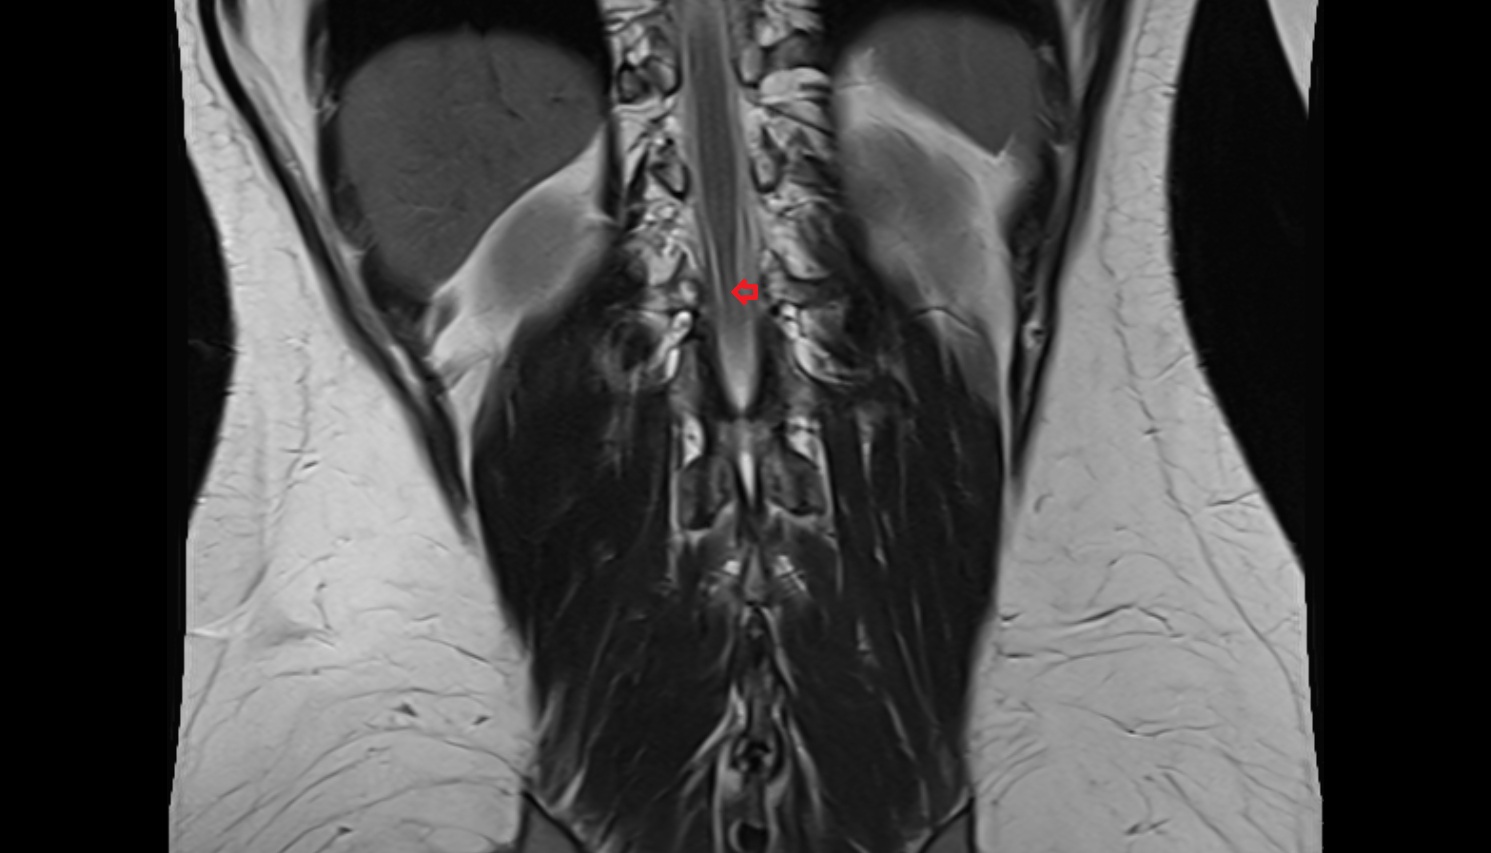

- Cauda equina

- Conus medullaris